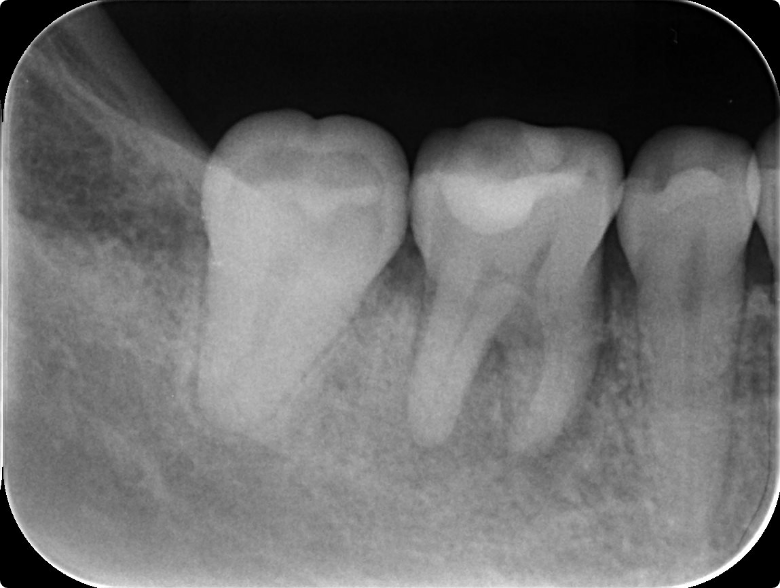

二次虫歯による感染根管治療を行った症例

BEFORE

AFTER

症例概要

年代、性別

50代女性

主訴

右下の歯が噛むと痛い

診断

根尖性歯周炎、歯周炎

治療内容

歯周基本治療、感染根管治療、ファイバーポストを用いた支台築造、フルジルコニアクラウン装着

治療期間

3ヶ月程度

治療リスク

噛み合わせの状態によっては歯根破折を起こすことがある

治療費用

275,000円(税込)